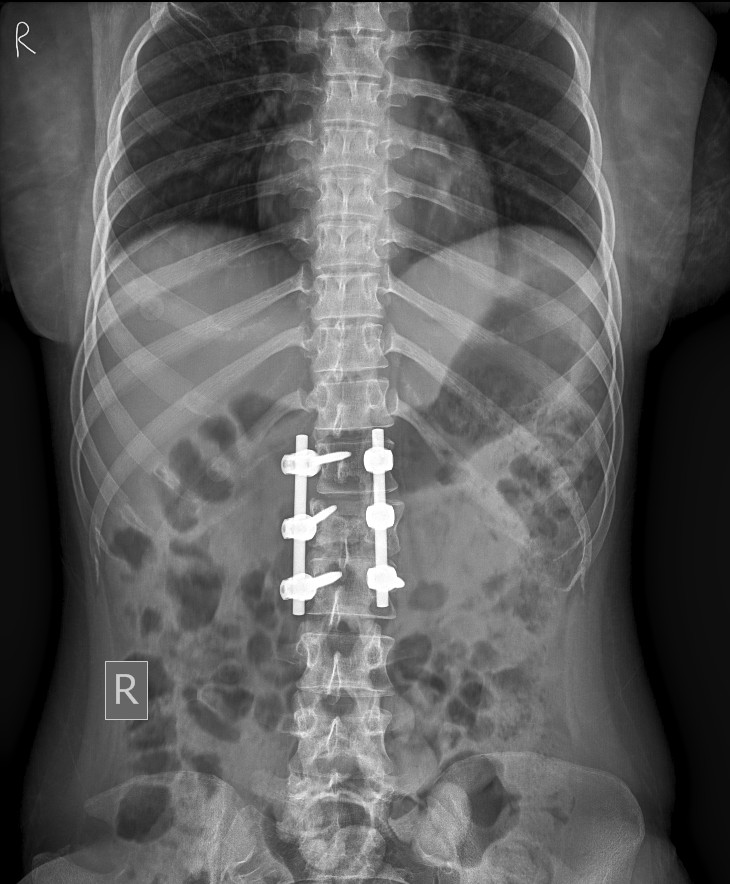

This also done by minimally invasive technique

Screws and rods for spine stabilisation are done under a special technique called image

intensification – again minimal tissue damage and faster recovery